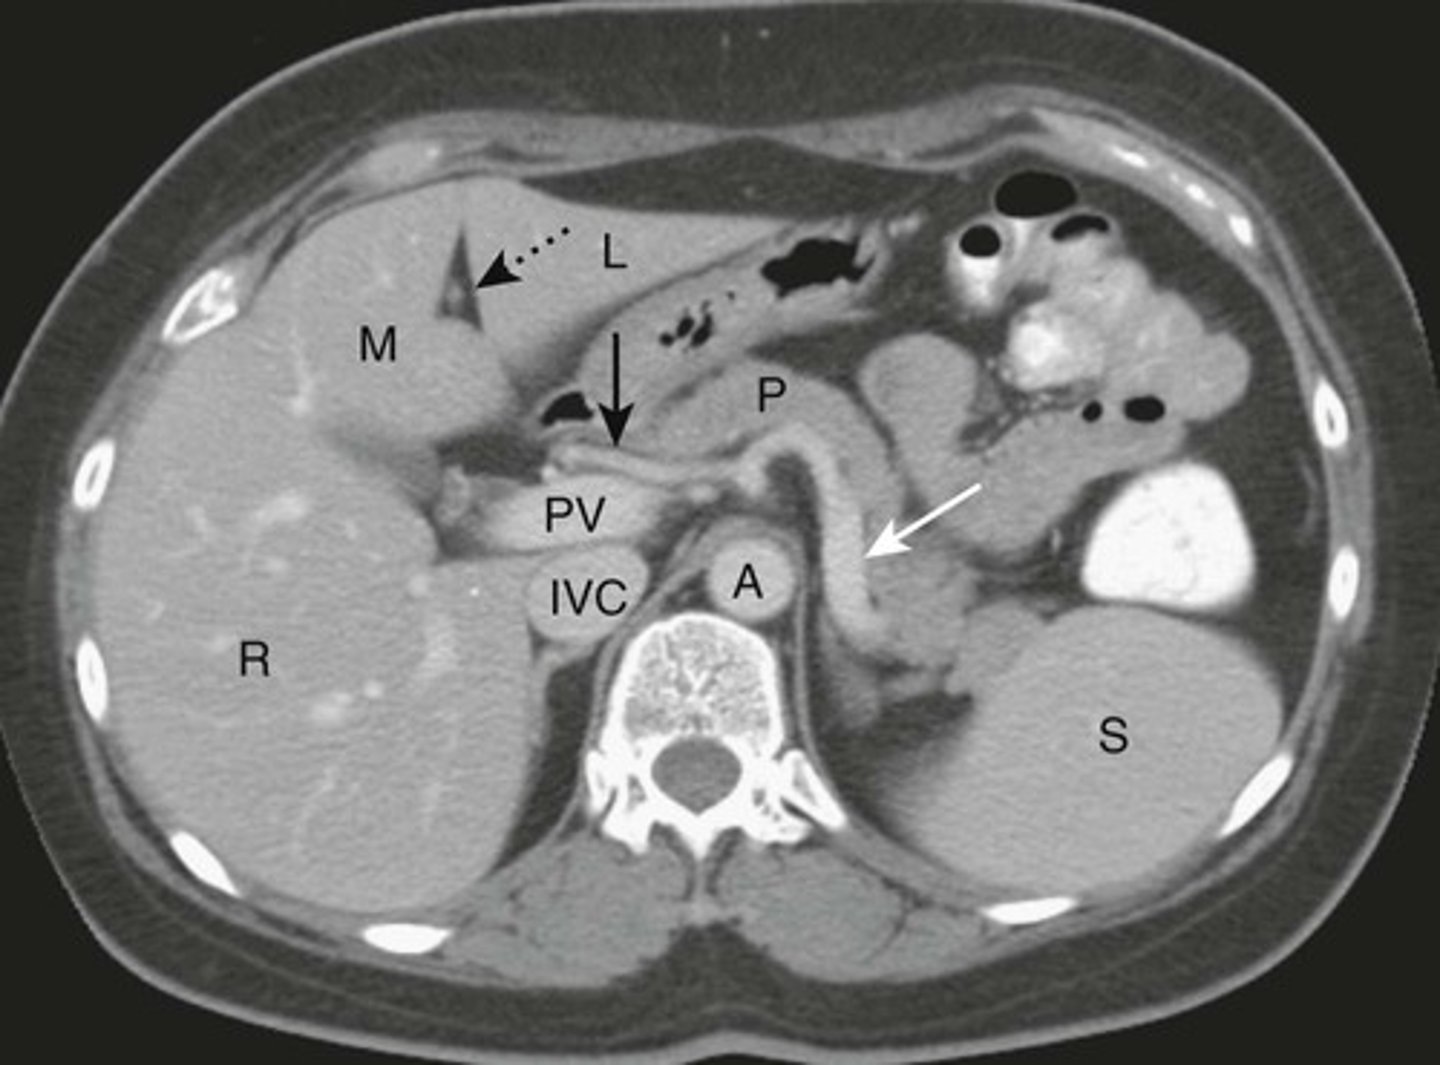

NORMAL LIVER ANATOMY

DOTTED BLACK ARROW:

Ligamentum teres - divides the left love of the liver into medial and latera segments, with larger right lobe more posterior.

M: Medial segment of left lobe

L: Lateral segment of left lobe

R: larger right lobe of liver.

PV: Portal vein, lying just posterior to the hepatic artery

SOLID BLACK ARROW: hepatic artery

SOLID WHITE ARROW: Splenic artery, follows the path of the pancreas towards the spleen

P: PANCREAS

S: Spleen

IVC: Inferior vena cava, lying right of the aorta

A: Aorta